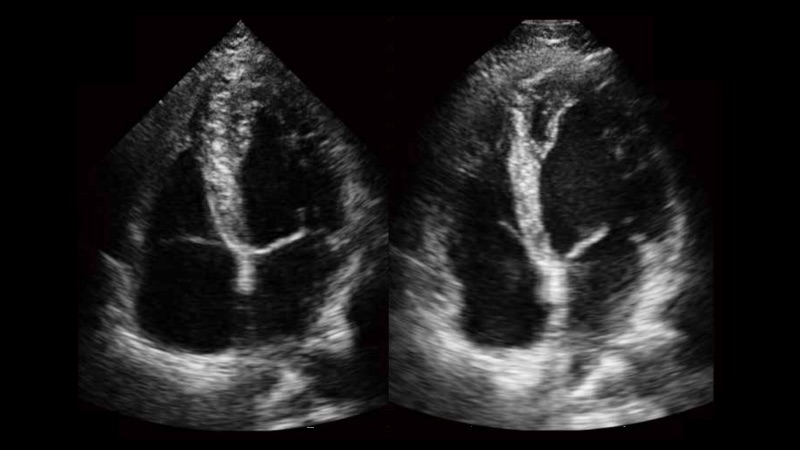

自動識別收縮和舒張末期心肌內(nèi)膜,自動計算射血分?jǐn)?shù)EF值。